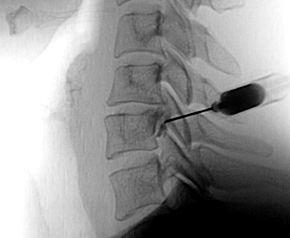

안정과 휴식을 취하면서 약물치료, 주사치료, 운동치료, 도수치료, 체외충격파 등을 복합적으로 시행합니다. 비수술치료시 신경차단술, 신경성형술, 협착부위 풍선확장술 등을

통해 질환을 호전시 킵니다.

비수술 치료에도 증상이 호전되지 않거나 보행 장애가 심각한 등 일상생활에 지장이 있다면 수술 치료를 시행하하며 양방향척추내시경 및 미세현미경레이져수술,

척추유합술 등을 통해 치료합니 다.